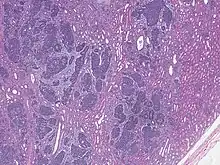

| High magnification micrograph showing the three elements of Wilms' tumor. H&E stain. | |

Pathologically, a triphasic nephroblastoma comprises three elements:[11]

- blastema

- mesenchyme (stroma)

- epithelium

Wilms' tumor is a malignant tumor containing metanephric blastema, stromal and epithelial derivatives. Characteristic is the presence of abortive tubules and glomeruli surrounded by a spindled cell stroma. The stroma may include striated muscle, cartilage, bone, fat tissue, and fibrous tissue. Dysfunction is caused when the tumor compresses the normal kidney parenchyma.